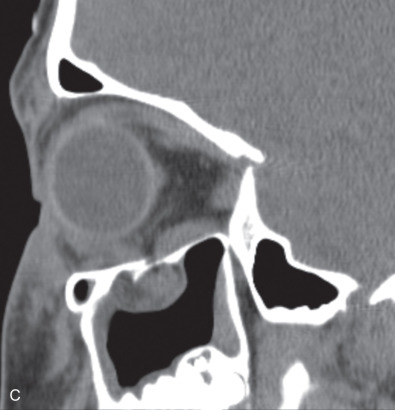

While comminuted “blow-out” fractures are commonly seen in adults, linear, minimally displaced fractures occur more commonly in the pediatric orbit. The elasticity of the pediatric orbital bone is the key difference, resulting in a unique clinical presentation: trapdoor fractures. The trapdoor pattern describes the entrapment of orbital tissue, the most concerning of which are extraocular muscles, in a linear orbital wall fracture that is usually minimally or non-displaced ( Fig. 2.3.4 ). When force is placed on the orbit, the intraorbital pressure increases and creates a fracture of the orbital wall. Periorbital tissue is then pushed into the open fracture. In the adult, the fracture remains open and displaced, resulting in the classic “blow-out” presentation characterized by enophthalmos and/or hypoglobus. In the pediatric patient, however, the bone fracture is incomplete, and the partially fractured bone will rapidly recoil back to the original position trapping the periorbital tissue and leading to possible strangulation. Furthermore, children presenting with radiographic “blow out” fractures often times do not present with globe malposition as do their adult counterparts ( Fig. 2.3.5 ). The periosteum and supporting soft tissue may remain intact, maintaining orbital volume despite a large displaced wall fracture.